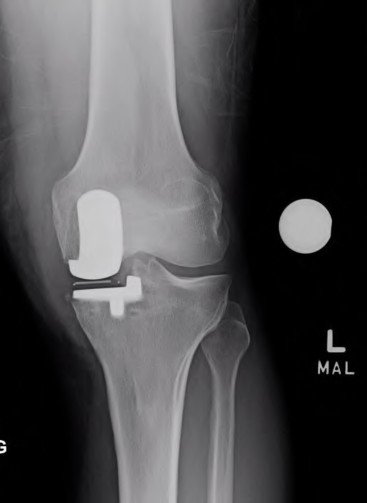

Question 1:

A 32-year-old female presents with knee pain. Radiographs show an eccentric, lytic epiphyseal lesion. Biopsy shows multinucleated giant cells and mononuclear stromal cells. Denosumab therapy is considered. What is the precise mechanism of action of Denosumab?

Correct Answer: Binds to RANKL, preventing interaction with RANK

Explanation:

Denosumab is a monoclonal antibody that specifically binds to RANKL (Receptor Activator of Nuclear factor Kappa-B Ligand). By binding to RANKL, it prevents it from interacting with the RANK receptor on the surface of osteoclasts and giant cells, thereby profoundly inhibiting osteoclastogenesis and tumor-associated bone lysis in giant cell tumors.